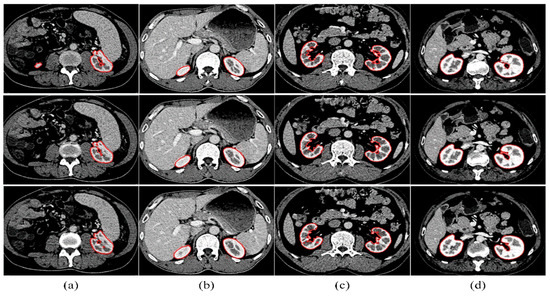

Through the above strategy, we select a kidney with a large area and a clear boundary as the initial contour and assume its slice as the initial segmentation slice. Figure 7 shows the search results of the initial kidney contours from four sequences. The first row displays the left kidney contour, and the second row displays the right.

Figure 7. (ad) Automatic searching results of the initial kidney contours from four sequences. The first row displays the left kidney contour, and the second row displays the right. The red outline represents the initial contour results.